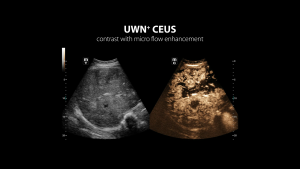

- UWN+Contrast - Mindray druhá generácia UWN CEUS )

Kontrastné zobrazovanie - UWN+ Kontrastné zobrazovanie: Ultraširokopásmové nelineárne plus kontrastné zobrazovanie

Kontrastné zobrazovanie QA - UWN+ Softvér na analýzu kvantifikácie kontrastu.

UWN+ (Ultra-Wideband Non-linear) kontrastné zobrazenie - CEUS: Excelentná citlivosť na kontrastnú látku aj s minimálnym signálom. Dlhší perfúzny čas s nižším MI. Lepšia vizualizácia perfúzie v jemných cievach s MFE ( Micro Flow Enhancement ). Presná diagnostika benígnych a malígnych tumorov. Výrazne zvyšuje mieru detekcie drobných lézií.

UWN+ (Ultra-Wideband Non-linear) kontrastné zobrazenie - CEUS: Excelentná citlivosť na kontrastnú látku aj s minimálnym signálom. Dlhší perfúzny čas s nižším MI. Lepšia vizualizácia perfúzie v jemných cievach s MFE ( Micro Flow Enhancement ). Presná diagnostika benígnych a malígnych tumorov. Výrazne zvyšuje mieru detekcie drobných lézií.

UWN+ (Ultra-Wideband Non-linear) kontrastné zobrazenie - CEUS: Excelentná citlivosť na kontrastnú látku aj s minimálnym signálom. Dlhší perfúzny čas s nižším MI. Lepšia vizualizácia perfúzie v jemných cievach s MFE ( Micro Flow Enhancement ). Presná diagnostika benígnych a malígnych tumorov. Výrazne zvyšuje mieru detekcie drobných lézií.

UWN+ (Ultra-Wideband Non-linear) kontrastné zobrazenie - CEUS: Excelentná citlivosť na kontrastnú látku aj s minimálnym signálom. Dlhší perfúzny čas s nižším MI. Lepšia vizualizácia perfúzie v jemných cievach s MFE ( Micro Flow Enhancement ). Presná diagnostika benígnych a malígnych tumorov. Výrazne zvyšuje mieru detekcie drobných lézií.

Kontrastné zobrazovanie - UWN+ Kontrastné zobrazovanie: Ultraširokopásmové nelineárne plus kontrastné zobrazovanie

Kontrastné zobrazovanie QA - UWN+ Softvér na analýzu kvantifikácie kontrastu.